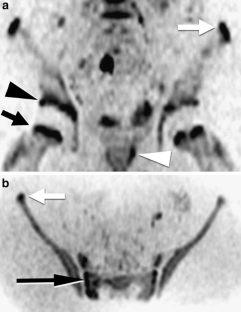

Fig. 1